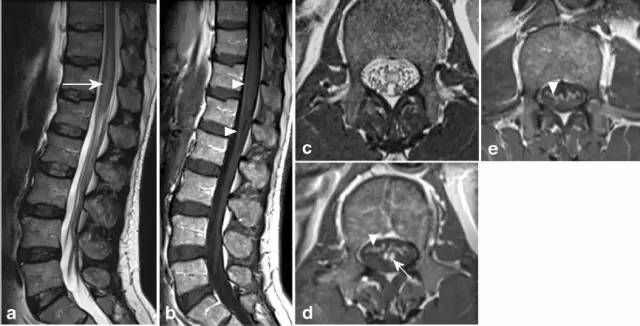

病例7:71岁男性,腹部外科手术后在ICU发生顽固低血压,导致脊髓前动脉分布区血流动力学性梗死。矢状位T2显示铅笔画样高信号(图a,箭头),轴位T2(图b-d)显示蛇眼征